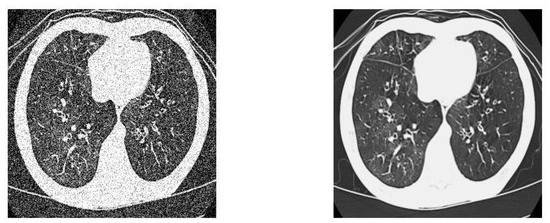

2.4.3. Discussion on Pneumonia X-ray Images

3.3. Experimental Analysis of ETLFOD Model for Pneumonia Dataset